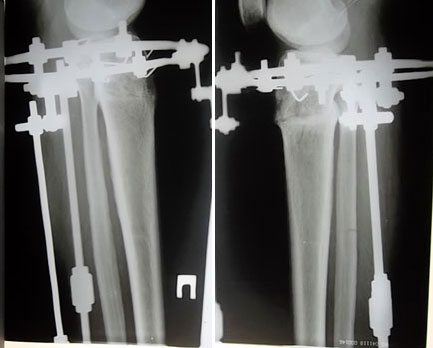

Диагноз: О-образная деформация нижних конечностей, ротация слева.

Вид операции: кортикотомия б/б кости верхней трети, наложение шарнирно - коррекционного - де ротационного аппарата Илизарова - Онипко.

рентгеновские снимки после операции, исправление деформации.

прямая проекция

SAM_3427.JPG

боковая проекция